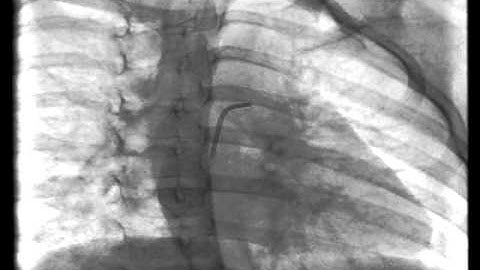

Nit-Occlud® Coil System for PDA Closure